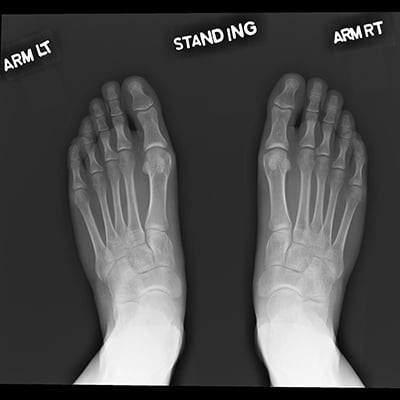

This module will help you achieve optimal images of the toes, foot, ankle, and calcaneus. Patient positioning, technical settings, and patient instructions are discussed. Descriptions and images of the expected anatomical structures are included, as well as image evaluation criteria.